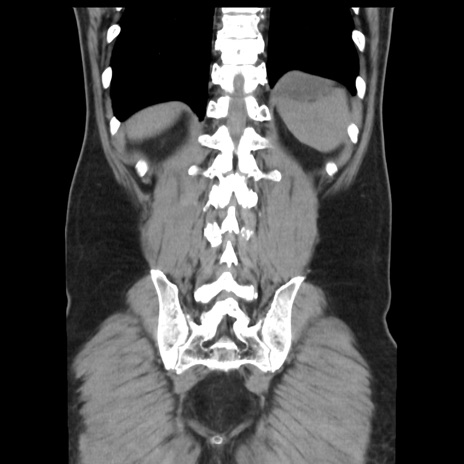

横断像